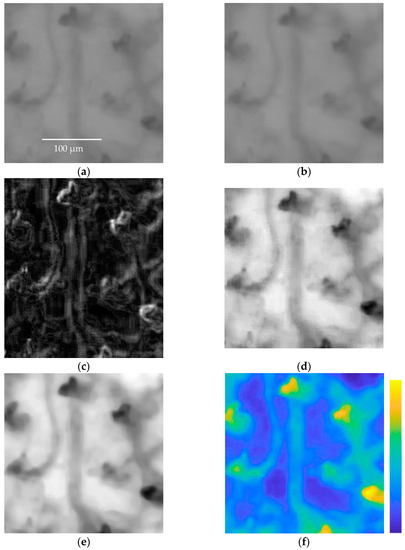

3.3. Signal Enhancement Process

- no preprocessing;

- enhancement;

- stabilization and enhancement.